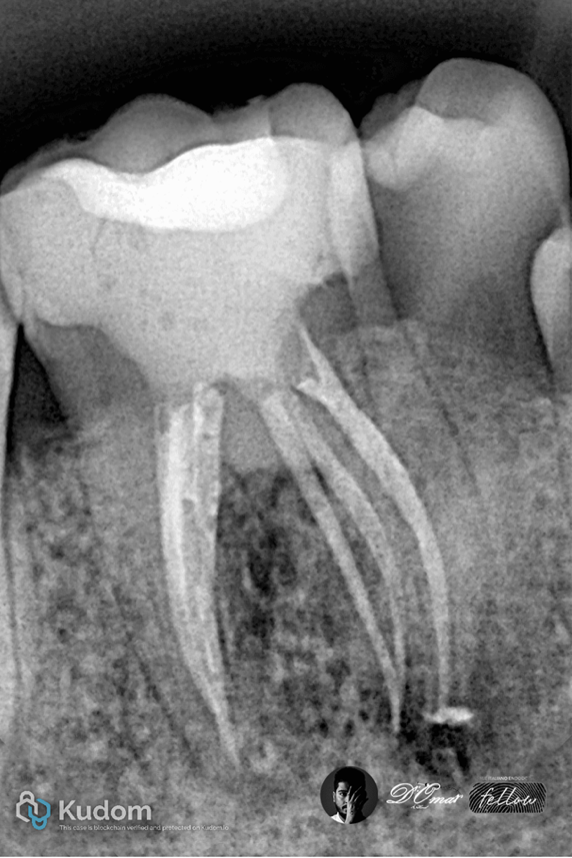

Fig. 6

Canal orifices were extremely narrow and difficult to locate

Complex curvatures increased the risk of file separation

Irrigant penetration was limited by multiple canal interconnections

Despite advanced irrigation and careful shaping, some areas remained mechanically untouched.

Fig. 7

Mesial shift PA x-ray show the

6 canals ..6 oraface and 3 roots